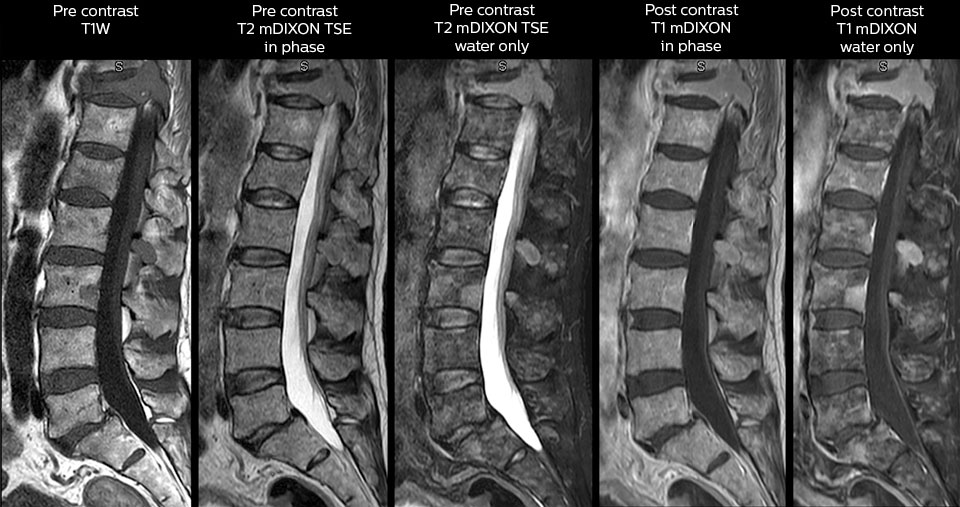

To minimize the time taken to perform scans, rapid MRI examination protocols (ExamCards) were developed, shortening the total scanning time to even less than 10 minutes in some exams. Techniques like mDIXON (modified DIXON) are used for robust capturing of fat-free MRI images in a hectic ED environment.

in image acquisition and postprocessing algorithms.”“mDIXON TSE sequences allow simultaneous characterization of morphological changes from the in-phase T2-weighted images and visualization of edematous changes, thanks to the water T2-weighted images from the same acquisition. Anatomical and morphological considerations could be a partial or complete ligament tear, a bony avulsion or hematoma.”

“mDIXON TSE sequences allow simultaneous characterization of morphological changes from the in-phase T2-weighted images and visualization of edematous changes, thanks to the water T2-weighted images from the same acquisition. Anatomical and morphological considerations could be a partial or complete ligament tear, a bony avulsion or hematoma.”

Including mDIXON TSE for robust fat suppression

“We use mDIXON TSE extensively in our spine imaging in the emergency room,” says Dr. Karis. “It’s particularly nice in that it is very robust with regard to susceptibility type of problems that would come up with traditional spectral fat-saturated images; these problems are essentially eliminated with the mDIXON technique. In our ED environment it’s really nice to have the fat-free imaging that goes along with the mDIXON technique.

“For the thoracic and cervical spine routine non-contrast exam, for example, we perform one mDIXON T2 TSE sequence, which provides us with two outputs: the fat-and-water-together T2-weighted images, as well as the water-only sagittal T2-weighted images. And then we also perform an axial gradient echo exam.”

Cervical spine routine exam

This patient presented with headache that was worse with neck flexion and we see a Chiari 1 malformation with low-lying cerebellar tonsils as well as some degenerative cervical thrombolytic change.